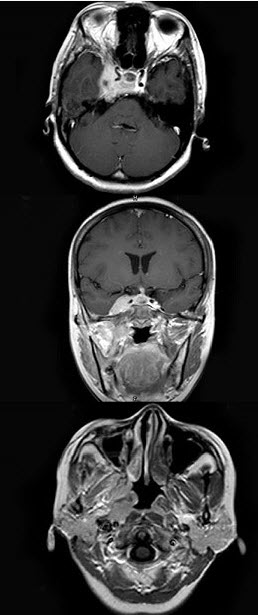

女,34岁。右侧听力下降,耳鸣2个月。MRI平扫及增强扫描如图示,最可能的诊断是()。

A、鼻咽癌

B、脑膜瘤

C、神经源性肿瘤

D、动脉瘤

E、未见异常

正确答案:

A